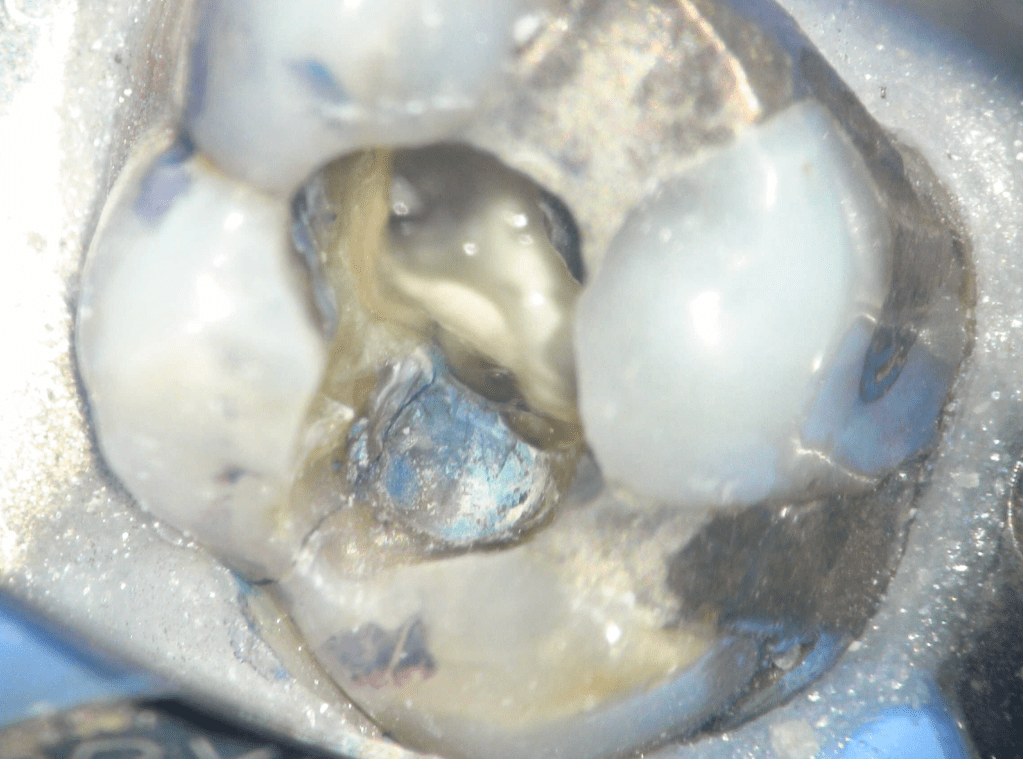

Fisura, remoción amalgama para explorar